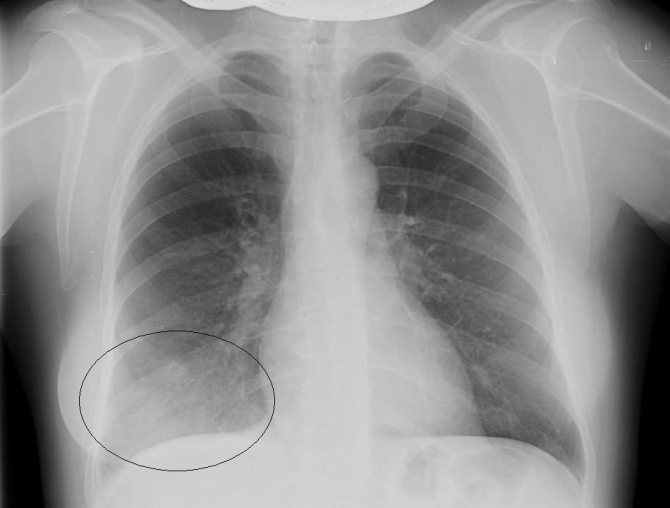

Постановка диагноза производится с использованием инструментальных способов, основным из которых является рентгенография. При крупозной пневмонии на снимках выявляют усиление легочного рисунка, расширение корня, изменение объема пораженной доли в большую сторону. При бронхопневмонии отмечается наличие одной или нескольких теней, каждая из которых по размеру не превышает полутора сантиметров. Тени могут сливаться. Рентгенографию проводят в прямой и боковой проекции, что повышает точность исследования.

Рентген снимок нижнедолевой пневмонии